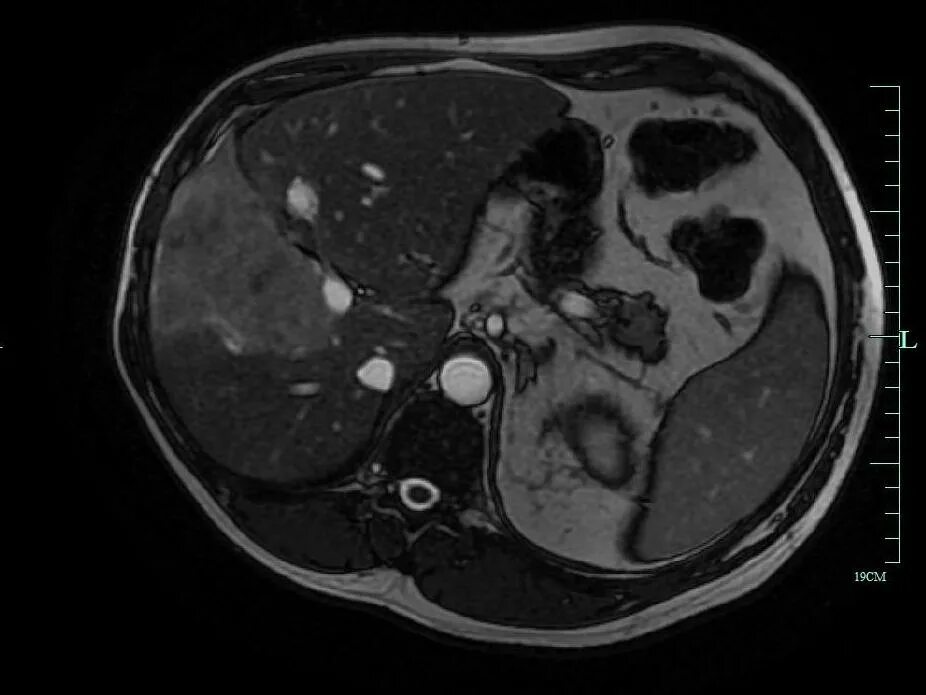

Цирроз печени кт